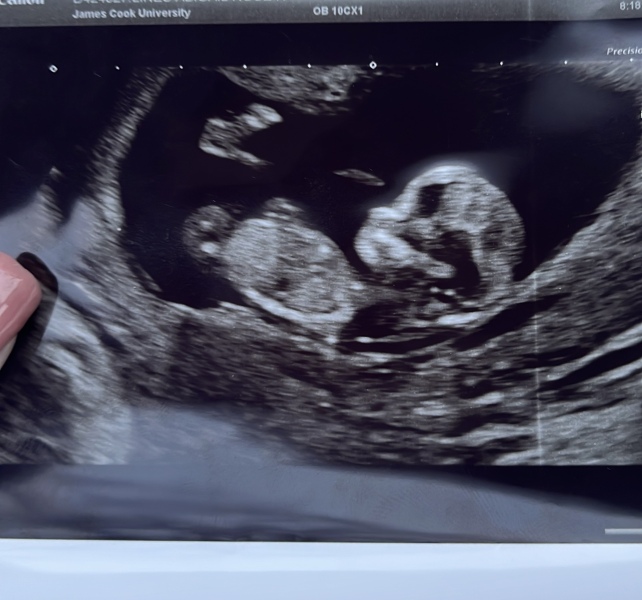

Had our reassurance scan today at 11+3. Our NHS scan isn't until 13 weeks so thought it would be nice to tell family Christmas Day with a cute picture 🥰🥰 xxx

Due July 2023

Aww how perfect @BabyGray 💕💕💕

That's a fab picture @BabyGray perfect for telling your family!